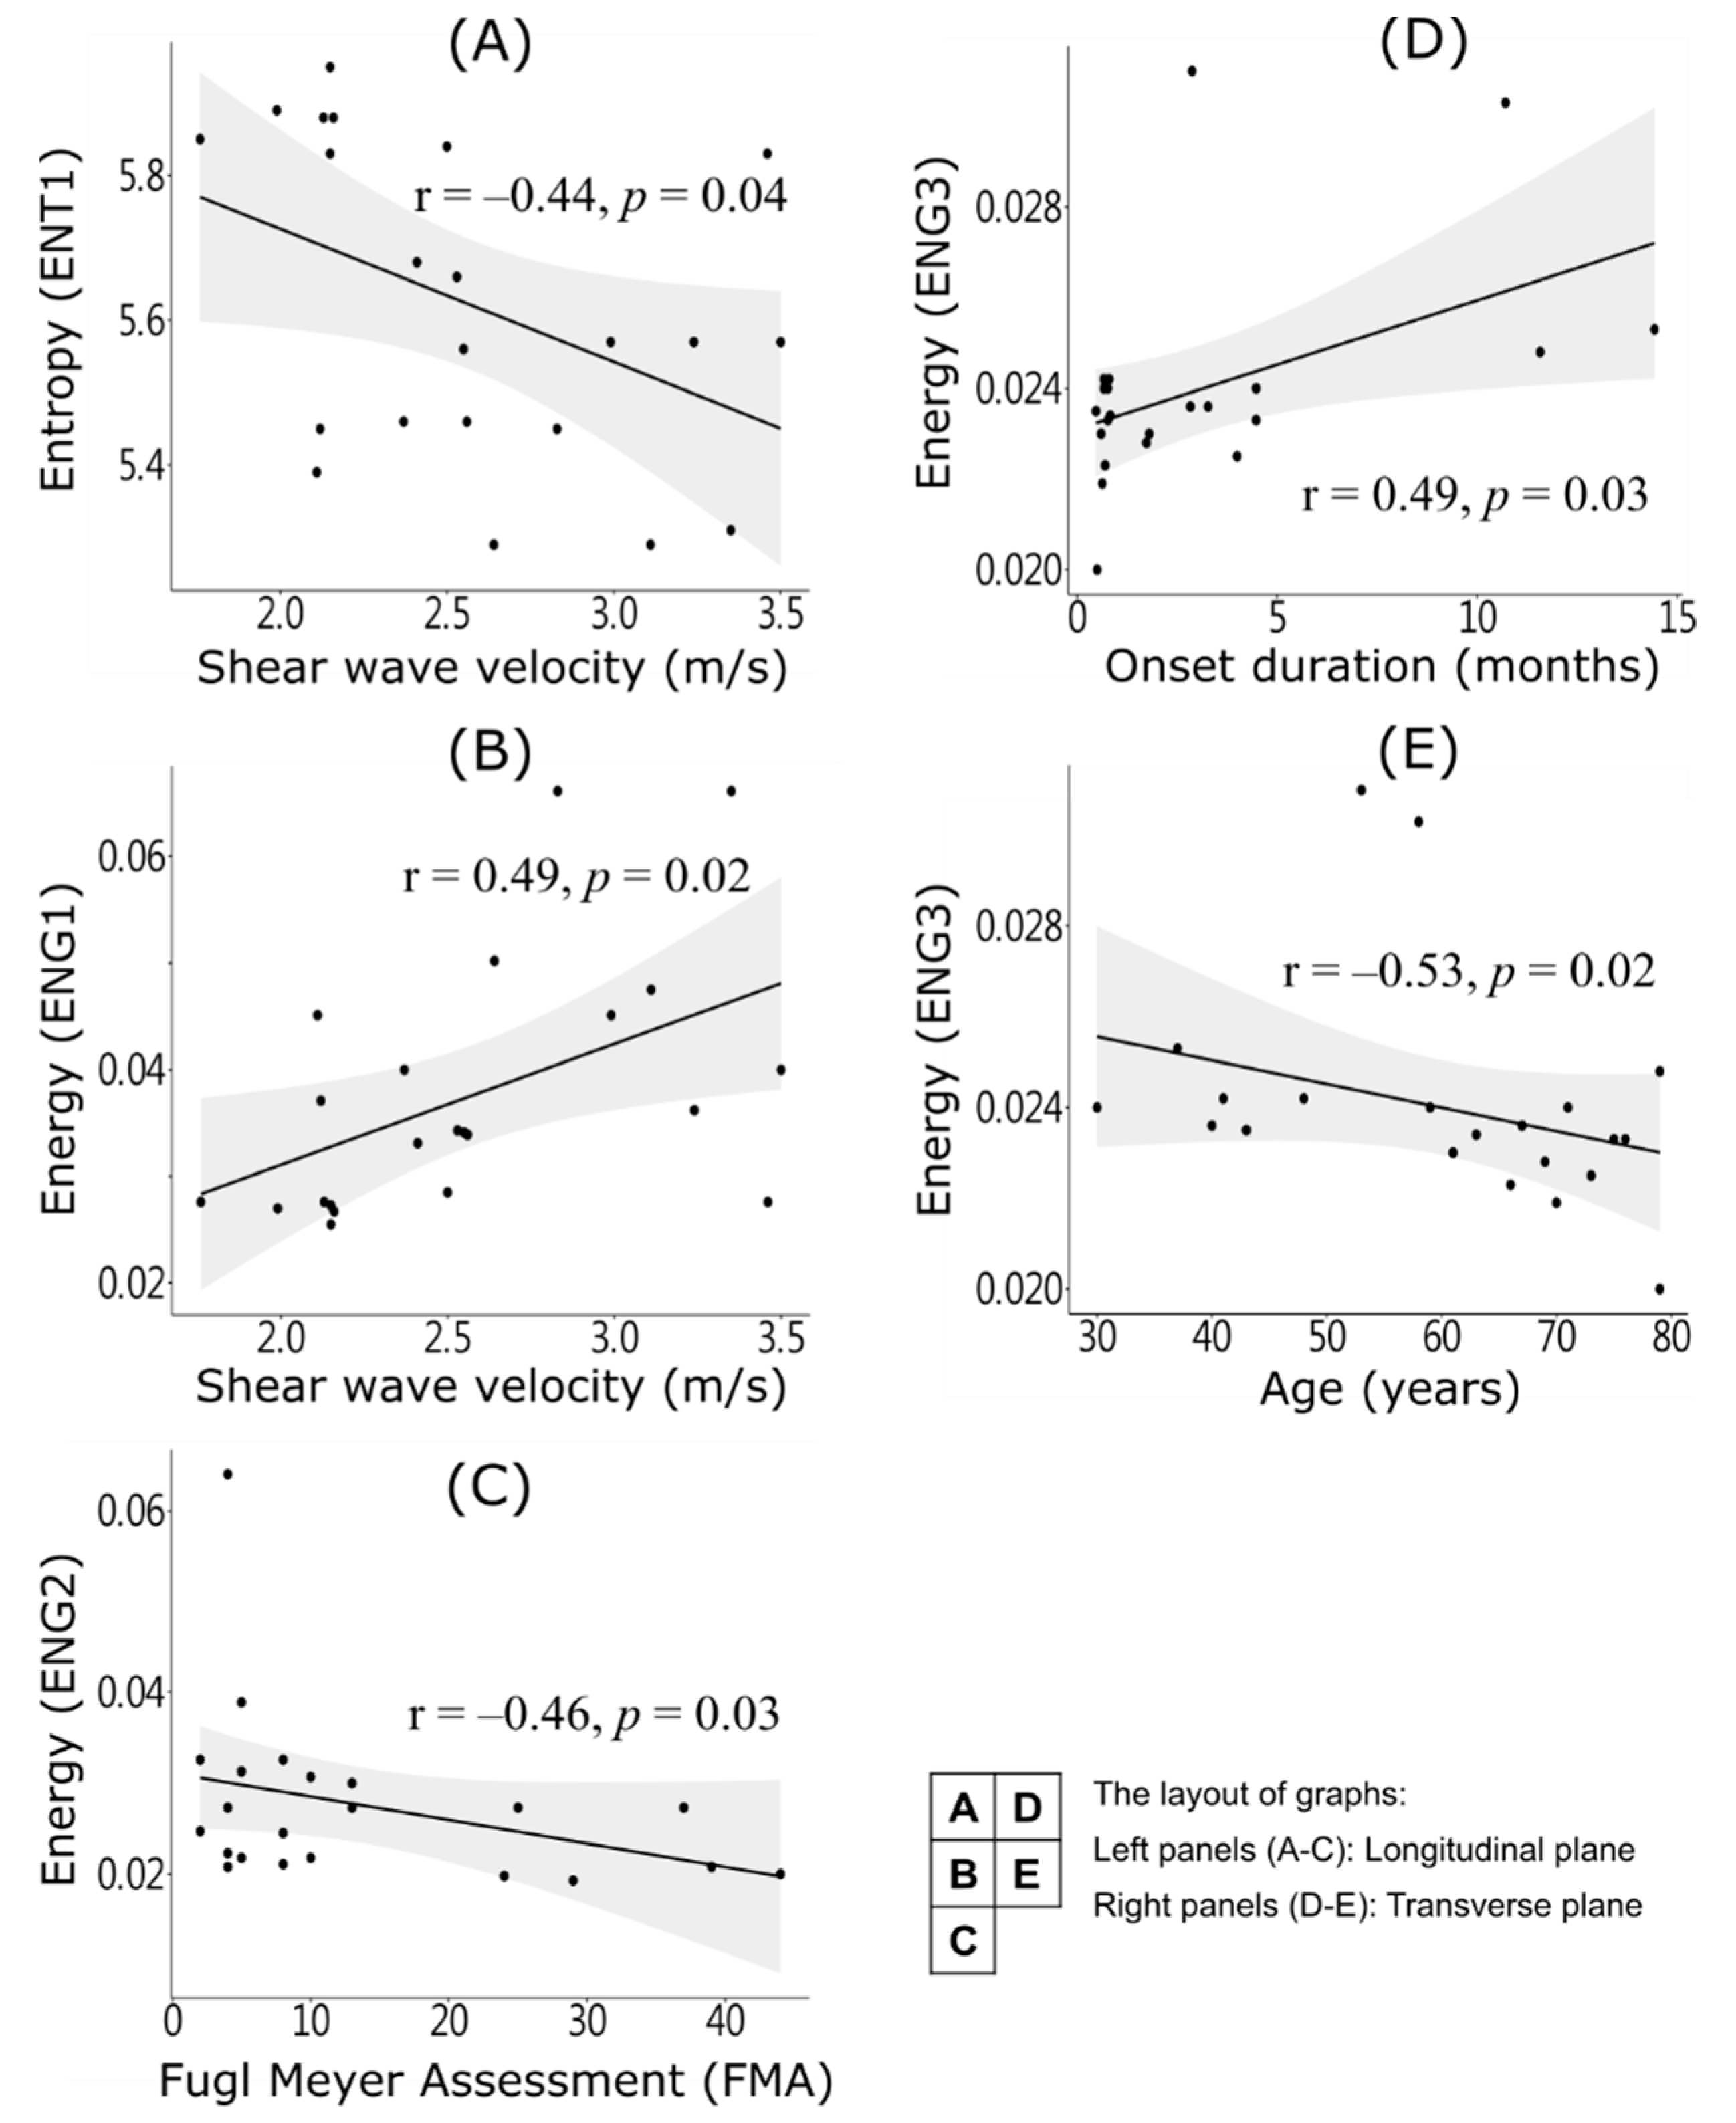

3. Results

4. Discussion

4.1. In-Homogenous Muscle Texture

4.2. Fiber Orientation and Shear Wave Velocity